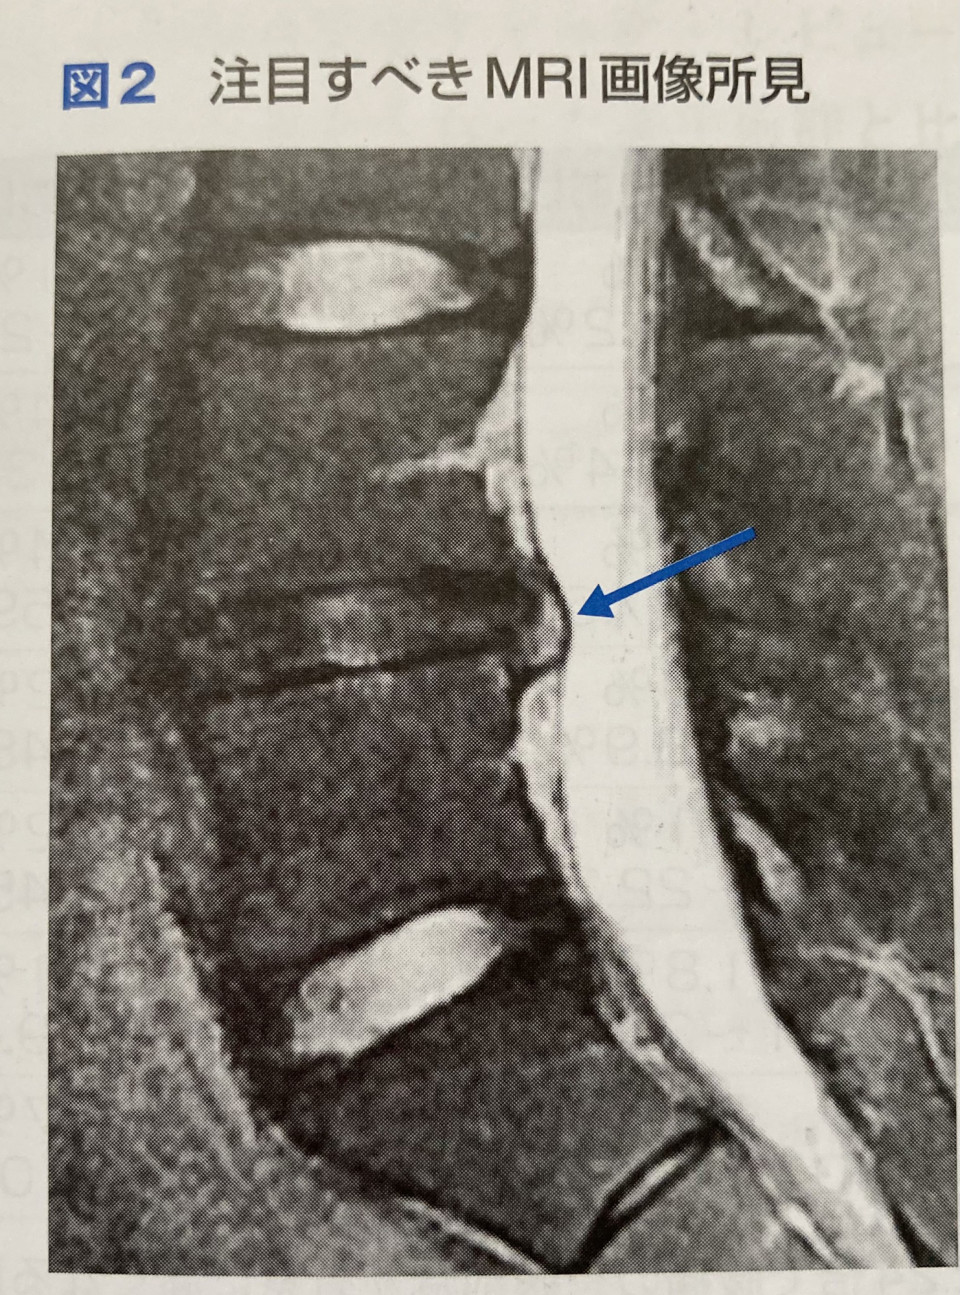

先日腰椎すべり症について書きましたが、すべり自体が根治することはないですが、症状を改善することができます。

すべり症とは腰椎が椎間板の変性などによって腰椎が前方に動いてしまうことで腰痛を引き起こしたり、脚に痛みやしびれ、筋力低下、感覚鈍麻などの神経症状が出ます。

4番目の腰椎がすべることが多く、腰を反ると腰痛を誘発します。立ち上がりの際、朝起きる時が痛いなどが患者さんの訴えとして多いのも特徴です。

腹筋群、骨盤底筋の筋力低下が続くと4番目の腰椎の前弯が強くなり椎間板が変性し腰椎が前方にすべるように移動します。

移動すると神経を挟み神経症状や腰椎が不安定になり腰を反らすと痛みが出ます。